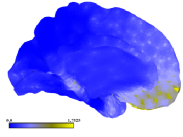

3.3 Methods Comparison

Figure 5 presents the L1 norm of B and C obtained for all our algorithm and datasets. Ten steps of refinement were conducted. At each step, five faces were subdivided and the algorithms run for ten optimization steps. Our results suggest that the tradeoff between the sparsity of B and C is different for the parameters selected. Because projected NMF do not control the sparsity of the loadings, PNMF basis tend to be very sparse but the projected loadings are not. The other factorization schemes balanced the L1 norms of B and C. For the parameters selected, the basis generated by dictionary learning were slightly sparser. We illustrate in figure 6 the results obtained when decomposing the myelin data using LE-PNNMF for a larger number of iterations. The basis obtained nicely decompose the map of large data variability into weakly overlapping components. The refinement had focused accordingly.